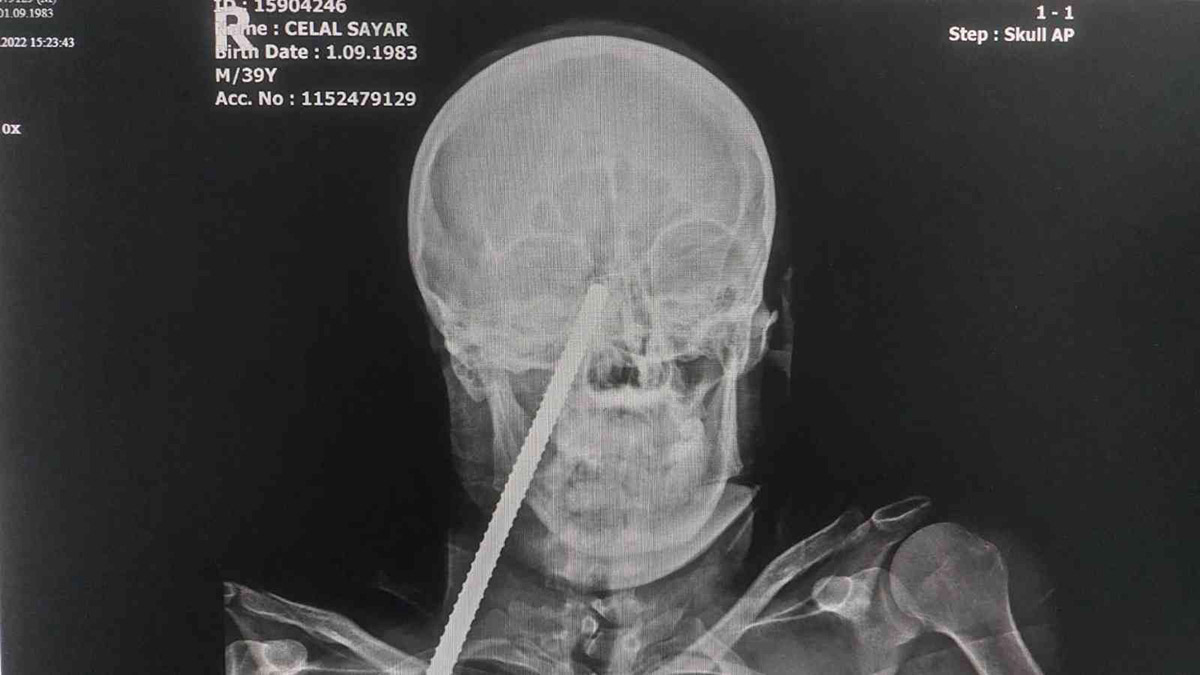

Edinilen bilgiye göre, Giresun’da çalıştığı inşaatta yüzüne demir saplanarak ölümden dönen 3 çocuk babası Celal Sayar (39), yüzündeki demir ile kaldırıldığı Giresun’daki hastaneden Samsun Eğitim ve Araştırma Hastanesine sevk edildi. Yüzüne saplanan demir Samsun’daki hastanede ameliyatla alınan Celal Sayar, yoğun bakım servisindeki tedavisinin ardından normal servise alındı.

Hastanenin kulak burun boğaz (KBB) servisinde tedavisi devam eden Celal Sayar yaşadığı olayı anlatarak, "İnşaatta ip çekmiştik. İpin ucunda demir bağlıydı. İpi çekince ipe bağlı demir yüzüme saplandı. Ben önce demir yüzüme çarptı zannettim" dedi.

Cemal Sayar’ın yüzüne saplanan inşaat demirinin ise ameliyatla çıkarıldıktan sonra polis tarafından Giresun Emniyet Müdürlüğüne gönderildiği öğrenildi.